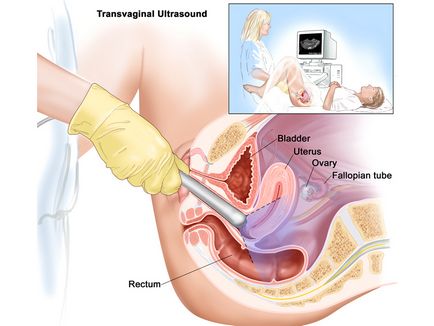

Ultrahang egy méhen kívüli terhesség

Amikor nyilvánvaló tünetei a kóros terhesség rendelt hüvelyen ultrahang. Ez a módszer lehetővé teszi kimutatását az embrió 3 héttel a fejlődés. nem ajánlott használni alapos ok nélkül, hogy ne provokálni a vetélés, amikor hirtelen a diagnózis rossz.

Vonatkozó rendszer transzvaginális ultrahang